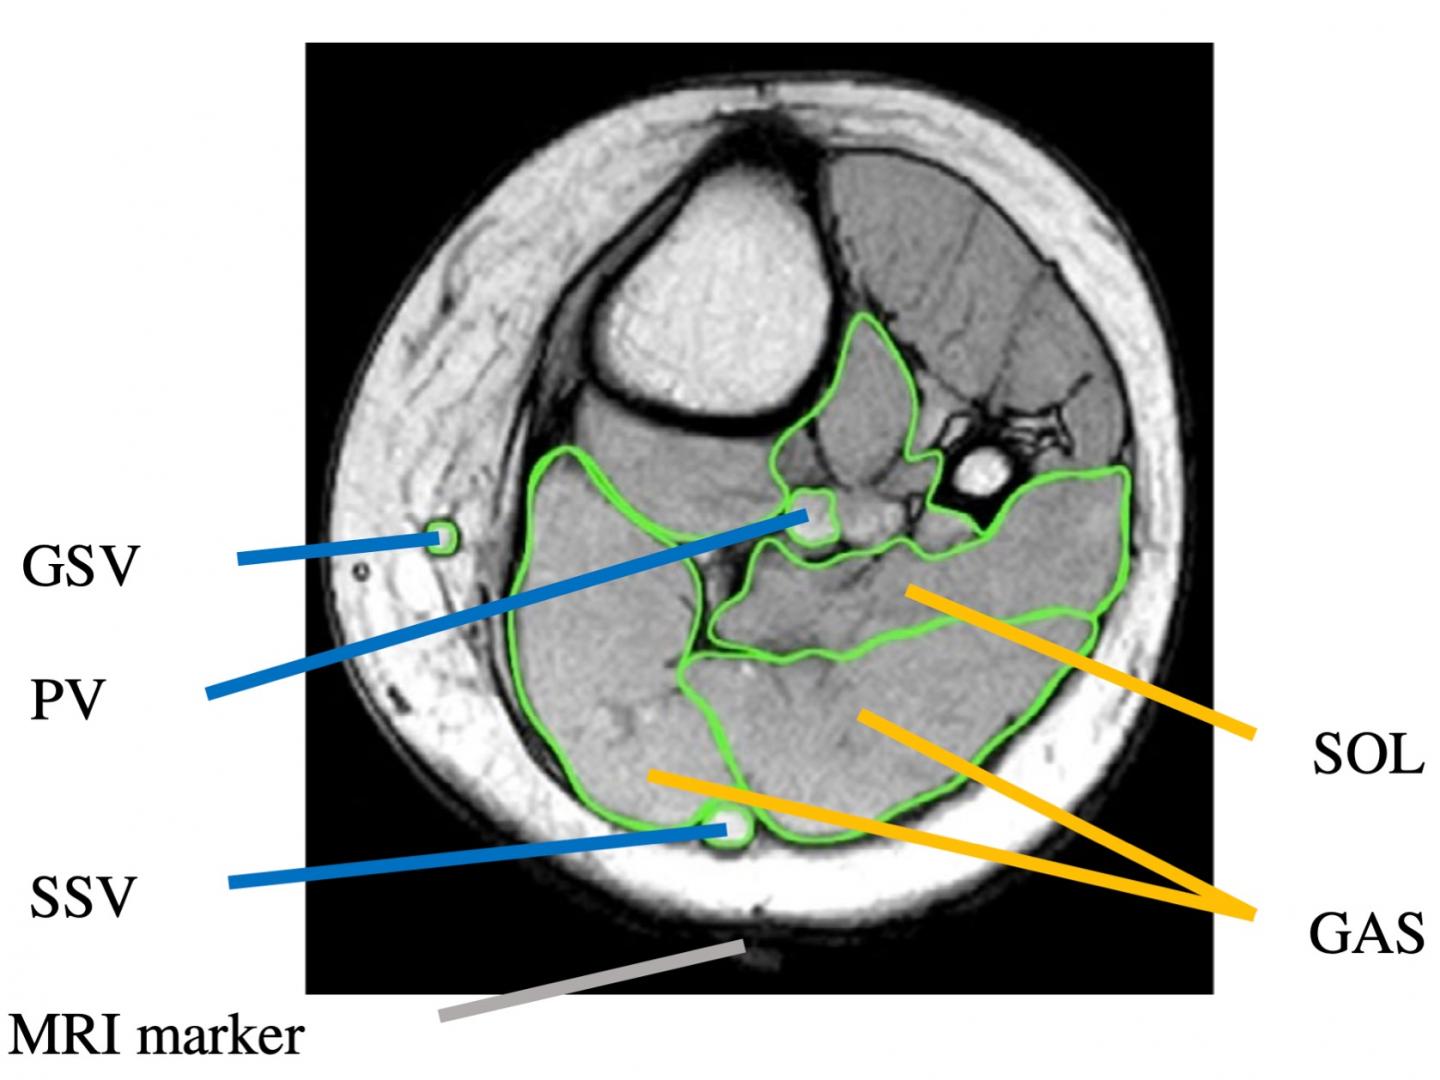

The lower leg muscles are essential bodily structures. Mri scans may be carried out for a variety of reasons, and will be accordingly targeted at specific zones of the body. Read on to learn more about the lower leg and lower extremity, including the bones, muscles, tendons, and nerves of the lower leg. You'll learn about the muscle. Your legs are two of your most important body parts. This may include the ankle, foot, and surrounding tissues. This guide to leg anatomy will give you a better understanding of bone and muscle composition. But even if you weren't born flexible, you can benefit from regularly stretching your leg muscles. Thank you, {{form.email}}, for signing up. Muscles are tissues that contract to help parts of the body move. They allow you to move and provide support for your upper body. Find out what you need to know about pelvic magnetic resonance imaging (mri), and discover what to expect, what the results can mean, and possible risks. The lower leg is a part of the lower extremity, or leg.

We'll break down the anatomy and function of the upper leg, knee, lower leg, ankle, and foot. Elizabeth quinn is an exercise physiologist, sports medicine writer, and fitness consultan. You'll learn about the muscle. Some people are naturally more flexible than others. What does the lower leg consist of? The lower leg is a part of the lower extremity, or leg. The lower leg muscles are essential bodily structures. It's a procedure that makes images of your. Find out what you need to know about pelvic magnetic resonance imaging (mri), and discover what to expect, what the results can mean, and possible risks. A leg mri (magnetic resonance imaging) scan of the leg uses strong magnets to create pictures of the leg. Muscles are tissues that contract to help parts of the body move. A leg mri (magnetic resonance imaging) scan of the leg uses strong magnets. Fans wonder if he needs to get his head checked out.